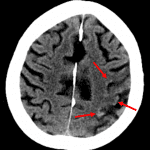

- Heterogeneous hypodensity and loss of gray-white differentiation in the posterior left frontal lobe and left insula with cortical-based curvilinear hyperdensity along the superior aspect

- Partial effacement of multiple left cerebral convexity sulci without midline shift, hydrocephalus, or evidence of herniation

- Sequela of chronic small vessel disease with global cerebral volume loss and ex vacuo dilation of the ventricular system

- Intracranial atherosclerosis

- Petechial hemorrhage vs cortical laminar necrosis

Likely subacute left MCA territory infarct with cortical-based curvilinear hyperdensity along the superior aspect consistent with cortical laminar necrosis and/or areas of petechial hemorrhage. No intraparenchymal hematoma.

Associated cytotoxic edema results in partial effacement of multiple left cerebral convexity sulci without midline shift, hydrocephalus, or evidence of herniation.

Sequela of chronic small vessel disease with global cerebral volume loss and ex vacuo dilation of the ventricular system. Intracranial atherosclerosis.